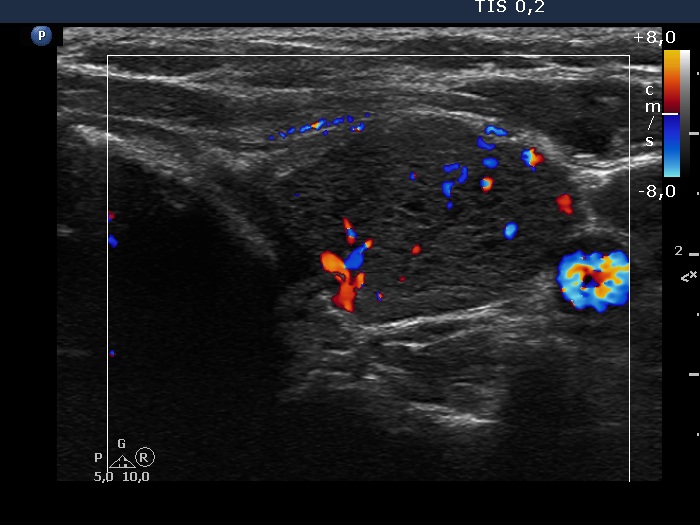

First examination (first, third and fifth rows of images):

Ultrasonography. The thyroid was echonormal and contained multiple inhomogeneous, partly blurred hypoechogenic and moderately hypoechogenic discrete lesions. Multiple lymph nodes were found on both sides of the neck.